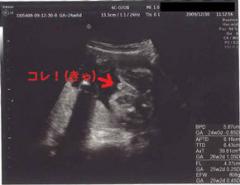

副院長:「とっても元気な男の子だね〜」

大サービスといわんばかりにたくさんのエコー写真をくれました(笑